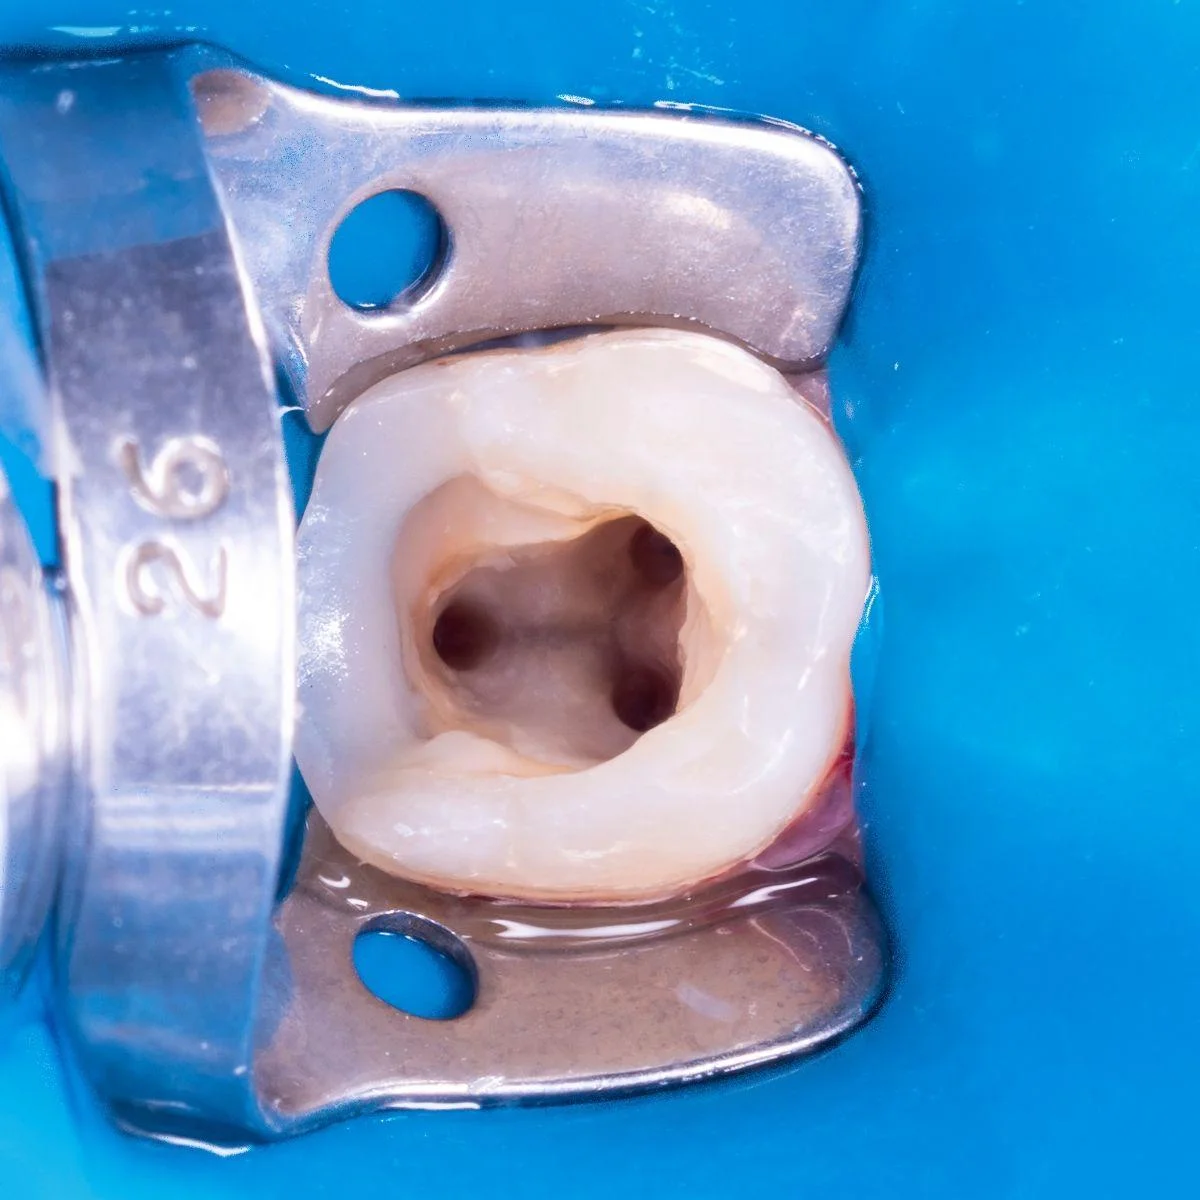

Endodontics is the treatment of root canals. As a result of the long-term development of caries, it deepens and creates inflammation of the neurovascular tissue in the dental canal, such inflammation is called pulpitis. After pulpitis, inflammation of the bone tissue around the root begins – periodontitis.

Endodontic treatment includes: cleaning the canals of the tooth from pathogenic microflora, their mechanical and chemical-ultrasonic treatment, sealing.

All medical procedures and especially endodontic interventions in our clinic are carried out using a dental microscope. When working under a microscope, the doctor sees the tooth under a magnification of 4 to 25 times and is additionally illuminated with a xenon beam, which contributes to maximum visualization and ensures a high-quality treatment result.